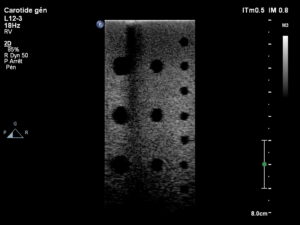

Avant réparation

Image avant réparation des cristaux